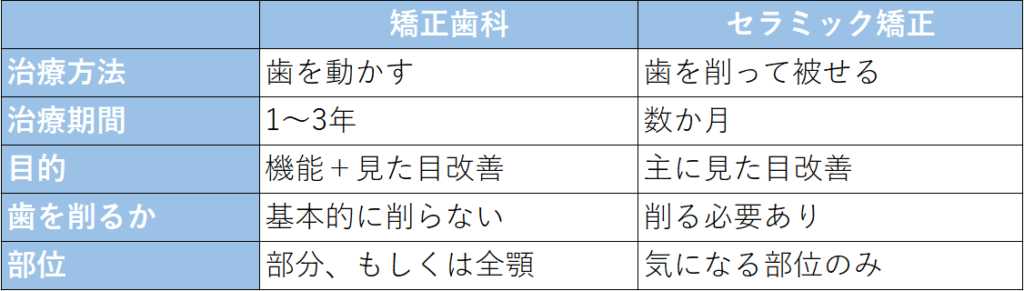

矯正歯科とセラミック矯正の比較表